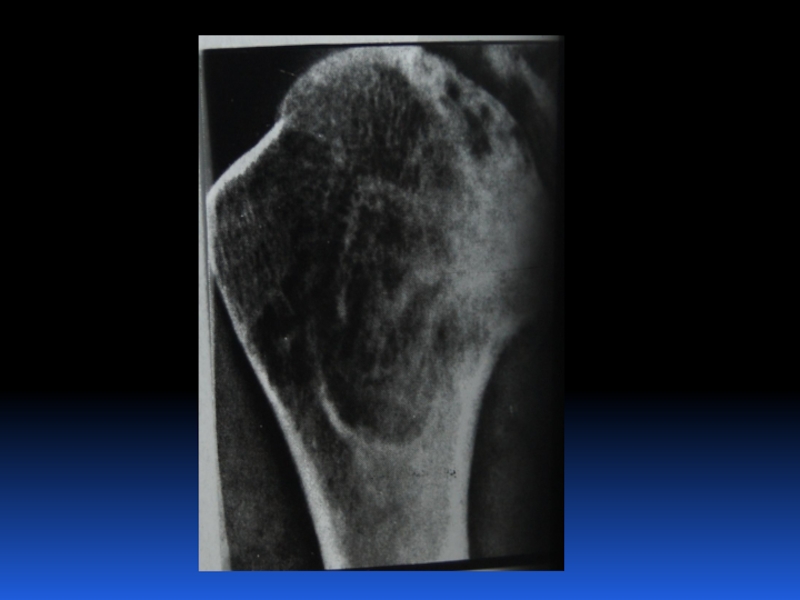

Остеопороз – это системное заболевание скелета, характеризующееся снижением костной массы и нарушением микроархитектоники костной ткани, с последующим увеличением хрупкости костей, со склонностью к патологическим переломам.

Слайд 2 Остеопороз – это системное заболевание скелета, характеризующееся снижением костной

массы и нарушением микроархитектоники костной ткани, с последующим увеличением хрупкости

костей, со склонностью к патологическим переломам.